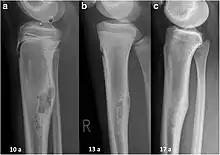

An arm bone tumor